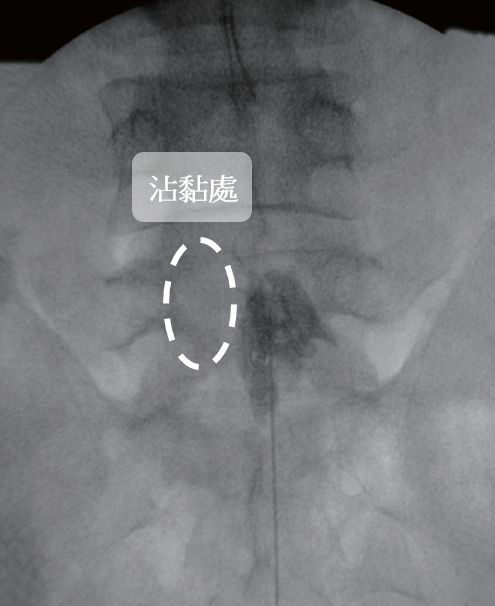

許安智說明,「硬脊膜外神經解沾黏術」利用X光機進行定位操作,會從靠近尾椎的薦椎裂孔先施以局部麻醉藥物並導入導管,再注入顯影劑分辨出沾黏處,接著針對沾黏處利用輕微剝離的方法將神經分離出來,減輕神經因沾黏造成的壓迫,最後注射消炎的藥物減緩疼痛,手術時間約一小時到兩小時(視部位多寡),病人全程保持清醒,過程中若感到不適可以立即向醫師反應,術後當日即可下床行走不用住院,不但傷口小於1公分,術後照顧也相對簡單。

▲手術患部出現「痠、痛、麻」感覺,可能是神經沾黏所引起的。